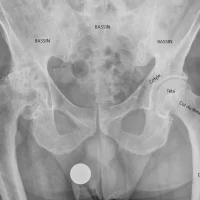

La fracture du col du fémur est l’une des fractures les plus fréquentes en traumatologie. Chaque année, le plus souvent à l’occasion d’une simple chute, plus de 80 000 personnes, dont une majorité de femmes de plus de 70 ans, en sont victimes. Le traitement de ces fractures est chirurgical dans la quasi totalité des cas. Le fémur forme le...